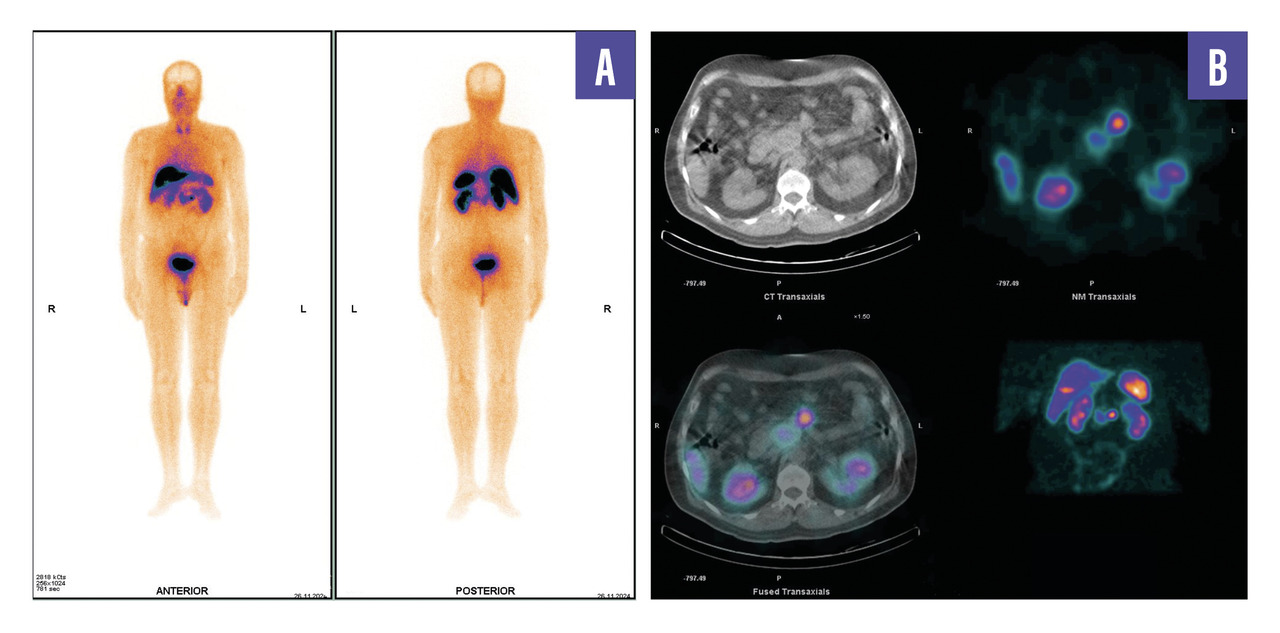

Un homme de 53 ans, sans antécédents, consulte pour des douleurs abdominales diffuses évoluant depuis plusieurs semaines. Le bilan biologique est normal. Une tomodensitométrie abdomino-pelvienne met en évidence une masse rétropéritonéale infiltrante associée à une adénopathie lombo-aortique. La tomographie par émission de positons (TEP-TDM au 18F-FDG) montre un hypermétabolisme léger de la lésion rétropéritonéale, mais l’adénopathie ne fixe pas le FDG (fig. 1). Un foyer hypermétabolique thyroïdien droit est également détecté. Une biopsie échoguidée confirme une tumeur neuro-endocrine digestive bien différenciée de grade 2 (Ki- 67 à 12 %). La scintigraphie au 99mTc-Tektrotyd révèle une fixation intense de l’adénopathie, compatible avec une pathologie neuro-endocrine exprimant les récepteurs de la somatostatine (fig. 2). Un nodule thyroïdien droit conduit à une thyroïdectomie totale, confirmant un microcarcinome papillaire.

L’association entre FRP et tumeur neuro-­endocrine (TNE) est exceptionnelle. Ce cas illustre une TNE bien différenciée, faiblement avide pour le FDG mais fixant intensément le 99mTc-Tektrotyd, combinée à un microcarcinome papillaire thyroïdien.

Ce cas souligne l’importance de l’imagerie métabolique et d’une approche intégrée pour le diagnostic et la prise en charge de pathologies complexes.2